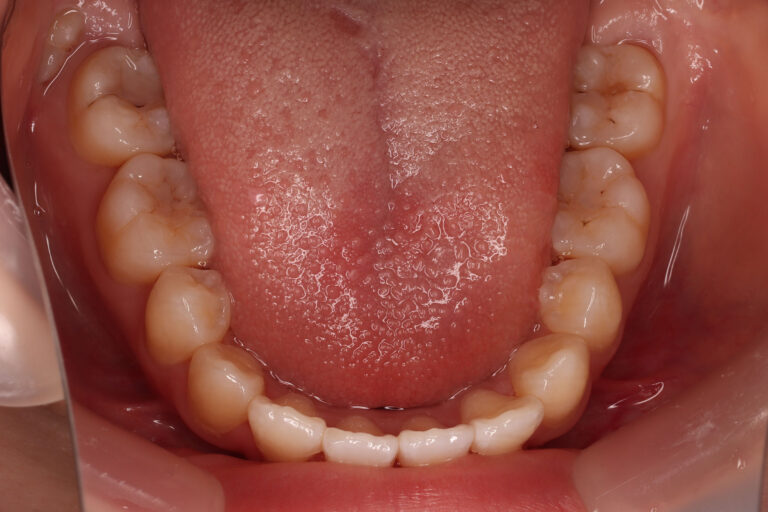

| 上下顎前突および前歯部に叢生(がたつき)がある患者さんです。 小児矯正で歯列の拡大を行った後、マルチブラケット装置での動的治療を開始しました。 口唇前突傾向改善のため、抜歯スペースを利用して治療しました。 抜歯スペースの方向に歯牙を移動させるため、前歯を前方傾斜させずに配列しています。 もし非抜歯で治療していたとしたら、また違った結果になっていたでしょう。 マルチブラケット装置での動的治療期間 2年4か月でした。 |